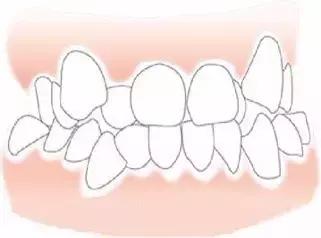

牙齿拥挤

牙齿拥挤的患者都需要进行牙齿矫正,但是牙齿拥挤本身就会造成牙龈萎缩。严重的牙齿拥挤会造成牙结石的堆积,从而造成长时间的牙龈炎症。牙齿排齐后,相邻间牙齿的间隙也就暴露出来,形成了黑三角。